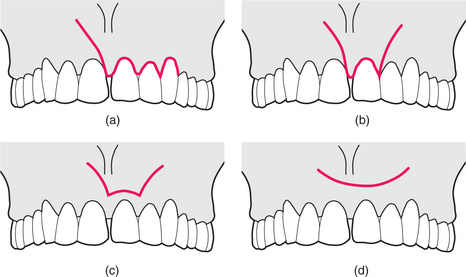

Flap design

There are three principal flap designs for surgical endodontics (Fig. 6.7):

‘two-sided’

‘three-sided’ (trapezoidal)

semilunar.

image

Fig. 6.7 (a) A two-sided flap, with a broad base and a gingival margin incision that can be extended around the gingival margin. (b) A three-sided flap, with divergent relieving incisions. (c) The Luebke-Ochsenbein flap, which aims to combine the benefit of avoiding the gingival margin, with the access provided by a three-sided flap. (d) The semilunar flap.

See also Chapter 4, pages 37–38.

‘Two-sided’ flap

A relieving incision is made in the oral mucosa of the buccal sulcus, and the incision is extended around the gingival margin of the tooth to be treated (Fig. 6.7a). Preservation of the gingival attachment is preferred wherever possible. An advantage of this type of incision is the ease of repositioning of the flap after surgery. In most circumstances access to the apical tissues is satisfactory. If access is not sufficient, the gingival margin incision can be extended distally as far as is required, but failing that, a second relieving incision may be used; the flap is now a three-sided design.

‘Three-sided’ (trapezoidal) flap

The three-sided flap (Figs 6.6, 6.7b) provides excellent access for most surgical endodontic procedures. There should be no undue tension on the flap while it is being retracted.

A modification of the three-sided flap leaves a 3- to 4-mm rim of gingival tissue in situ. This design (the so-called Luebke-Ochsenbein flap design) usually provides satisfactory access to the apical tissues (Fig. 6.7c). Although this flap is prone to wound dehiscence, it usually gives a good aesthetic result.

Semilunar flap

The semilunar design avoids the gingival margin, and there is less risk of recession of the gingival tissues after surgery (Fig. 6.7d). However, there are three main disadvantages of the semilunar flap design:

surgical access to the apical tissues may be restricted

it is often difficult to ensure the incision line ends up resting on bone

the flap sometimes results in wound dehiscence.